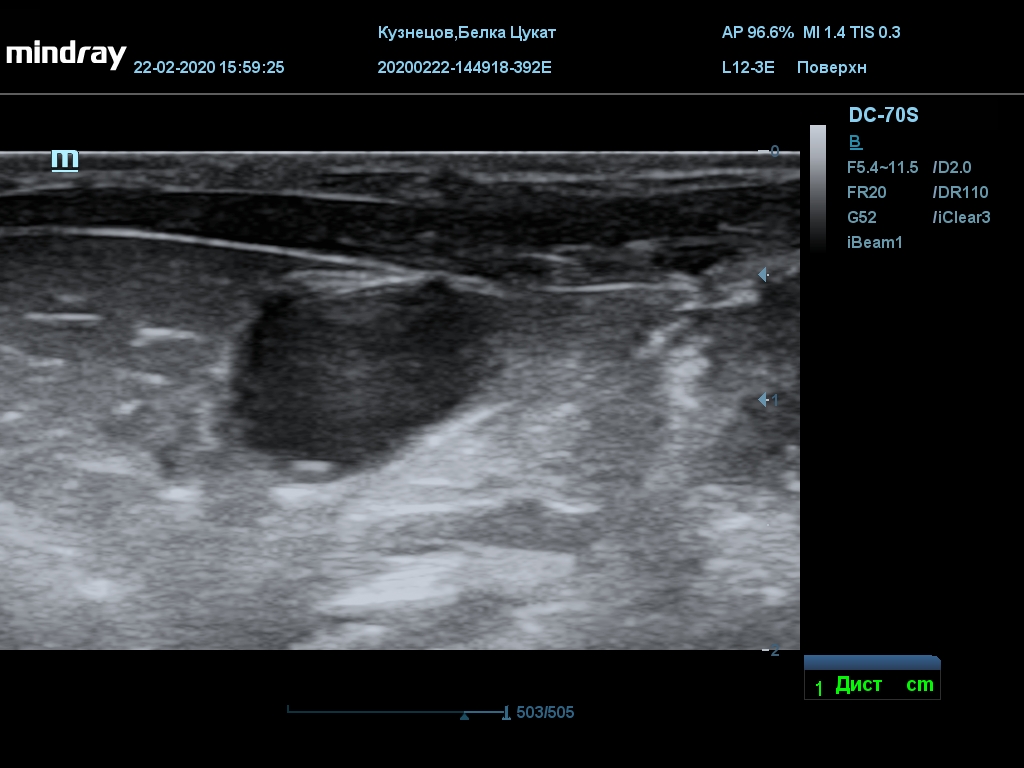

УЗИ

(почки, мочевой пузырь и, предположительно, простата)

Обращаю внимание, что делала УЗИ и писала заключение узист, которая специализируется на кошках и собаках, поэтому она сделала узи и описала, как смогла, но тонкостей грызунячьей анатомии она не знает.

Приложил только фото, есть ещё пара видео, но не знаю, как тут выложить, и надо ли.

Мочевой пузырь объём 12,1 х 7,6 х 11 мм. Стенка не утолщена, 0,5 мм, содержимое не однородное, до половины объёма гипоэхогенная мелкодисперсная взвесь. Макс. размер включений 0,8 мм. Теней нет.

Каудальнее мочевого пузыря визуализируется округлая структура размером 11,1 х 8,3 мм с ровными контурами гипоэхогенная однородная, с признаками васкуляризации.

Почка левая ровная, размер 12 х 7,6 х 8,2 мм. Контур ровный чёткий. КМД отсутствует, лоханка расширена незначительно, объёмных включений не выявлено.

Почка правая ровная, контур чёткий, размер 13,5 х 8,7 х 9,3 мм. Капсула визуализируется. КМД отсутствует, лоханка не расширена. Объёмные образования не выявлены.

Заключение: УЗпризнаки уролитиаза, объёмная структура каудальнее мочевого пузыря. Признаки расширения левой лоханки.

УЗИ

(почки, мочевой пузырь и, предположительно, простата)

Обращаю внимание, что делала УЗИ и писала заключение узист, которая специализируется на кошках и собаках, поэтому она сделала узи и описала, как смогла, но тонкостей грызунячьей анатомии она не знает.

Приложил только фото, есть ещё пара видео, но не знаю, как тут выложить, и надо ли.

Мочевой пузырь объём 12,1 х 7,6 х 11 мм. Стенка не утолщена, 0,5 мм, содержимое не однородное, до половины объёма гипоэхогенная мелкодисперсная взвесь. Макс. размер включений 0,8 мм. Теней нет.

Каудальнее мочевого пузыря визуализируется округлая структура размером 11,1 х 8,3 мм с ровными контурами гипоэхогенная однородная, с признаками васкуляризации.

Почка левая ровная, размер 12 х 7,6 х 8,2 мм. Контур ровный чёткий. КМД отсутствует, лоханка расширена незначительно, объёмных включений не выявлено.

Почка правая ровная, контур чёткий, размер 13,5 х 8,7 х 9,3 мм. Капсула визуализируется. КМД отсутствует, лоханка не расширена. Объёмные образования не выявлены.

Заключение: УЗпризнаки уролитиаза, объёмная структура каудальнее мочевого пузыря. Признаки расширения левой лоханки.